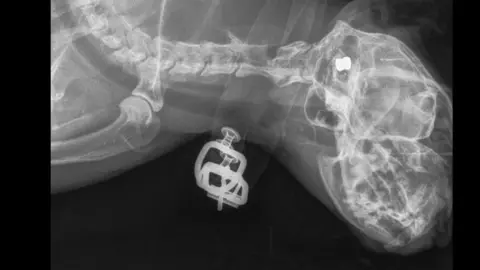

RSPCA inspector Thomas Hutton said: "Dusty was previously shot in the leg with an airgun, back in November, and the pellet removed by vets."